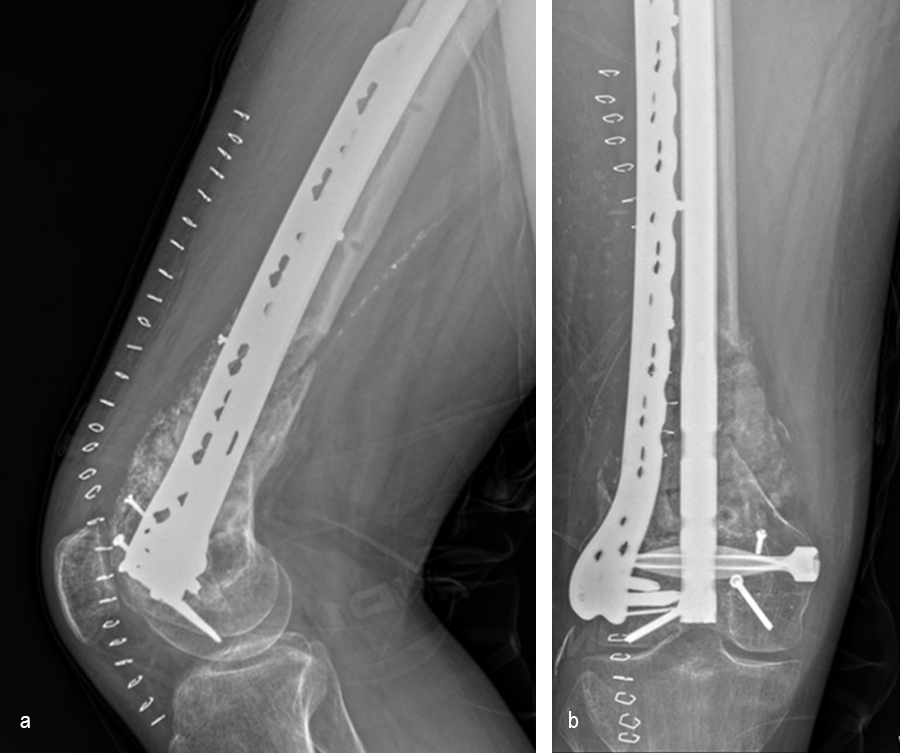

The second stage of surgery took place in October 2022. The cage was inserted (Figs 20-22) and filled with ~20cc autograft obtained by RIA of the femur, 30cc allograft and 3cc BMAC.

Healing progressed well over the following 9 months (Fig 23 - 27). The patient’s pain was well controlled in the early postoperative phase, and he was weaned off the prescribed narcotics after four weeks. He remained smoke free for the first four weeks and then admitted to re-starting his vaping. His elbow ROM improved significantly to 20-125 and good supination/pronation.